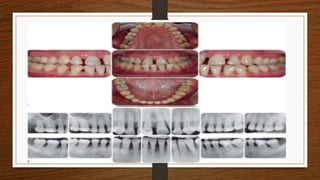

RADIOGRAPHIC & CLINICAL FINDINGS

• Vertical loss of alveolar bone around the first molars and incisors

• Beginning around puberty in otherwise healthy teenagers, is a classic diagnostic sign of LAP

• Arc shaped loss of alveolar bone extending from distal surface of the second premolar to

the mesial surface of the second molar

• Vertical lossof alveolar bone around the first molars and incisors • Beginning around puberty in otherwise healthy teenagers, is a classic diagnostic sign of LAP • Arc shaped loss of alveolar bone extending from distal surface of the second premolar to the mesial surface of the second molar